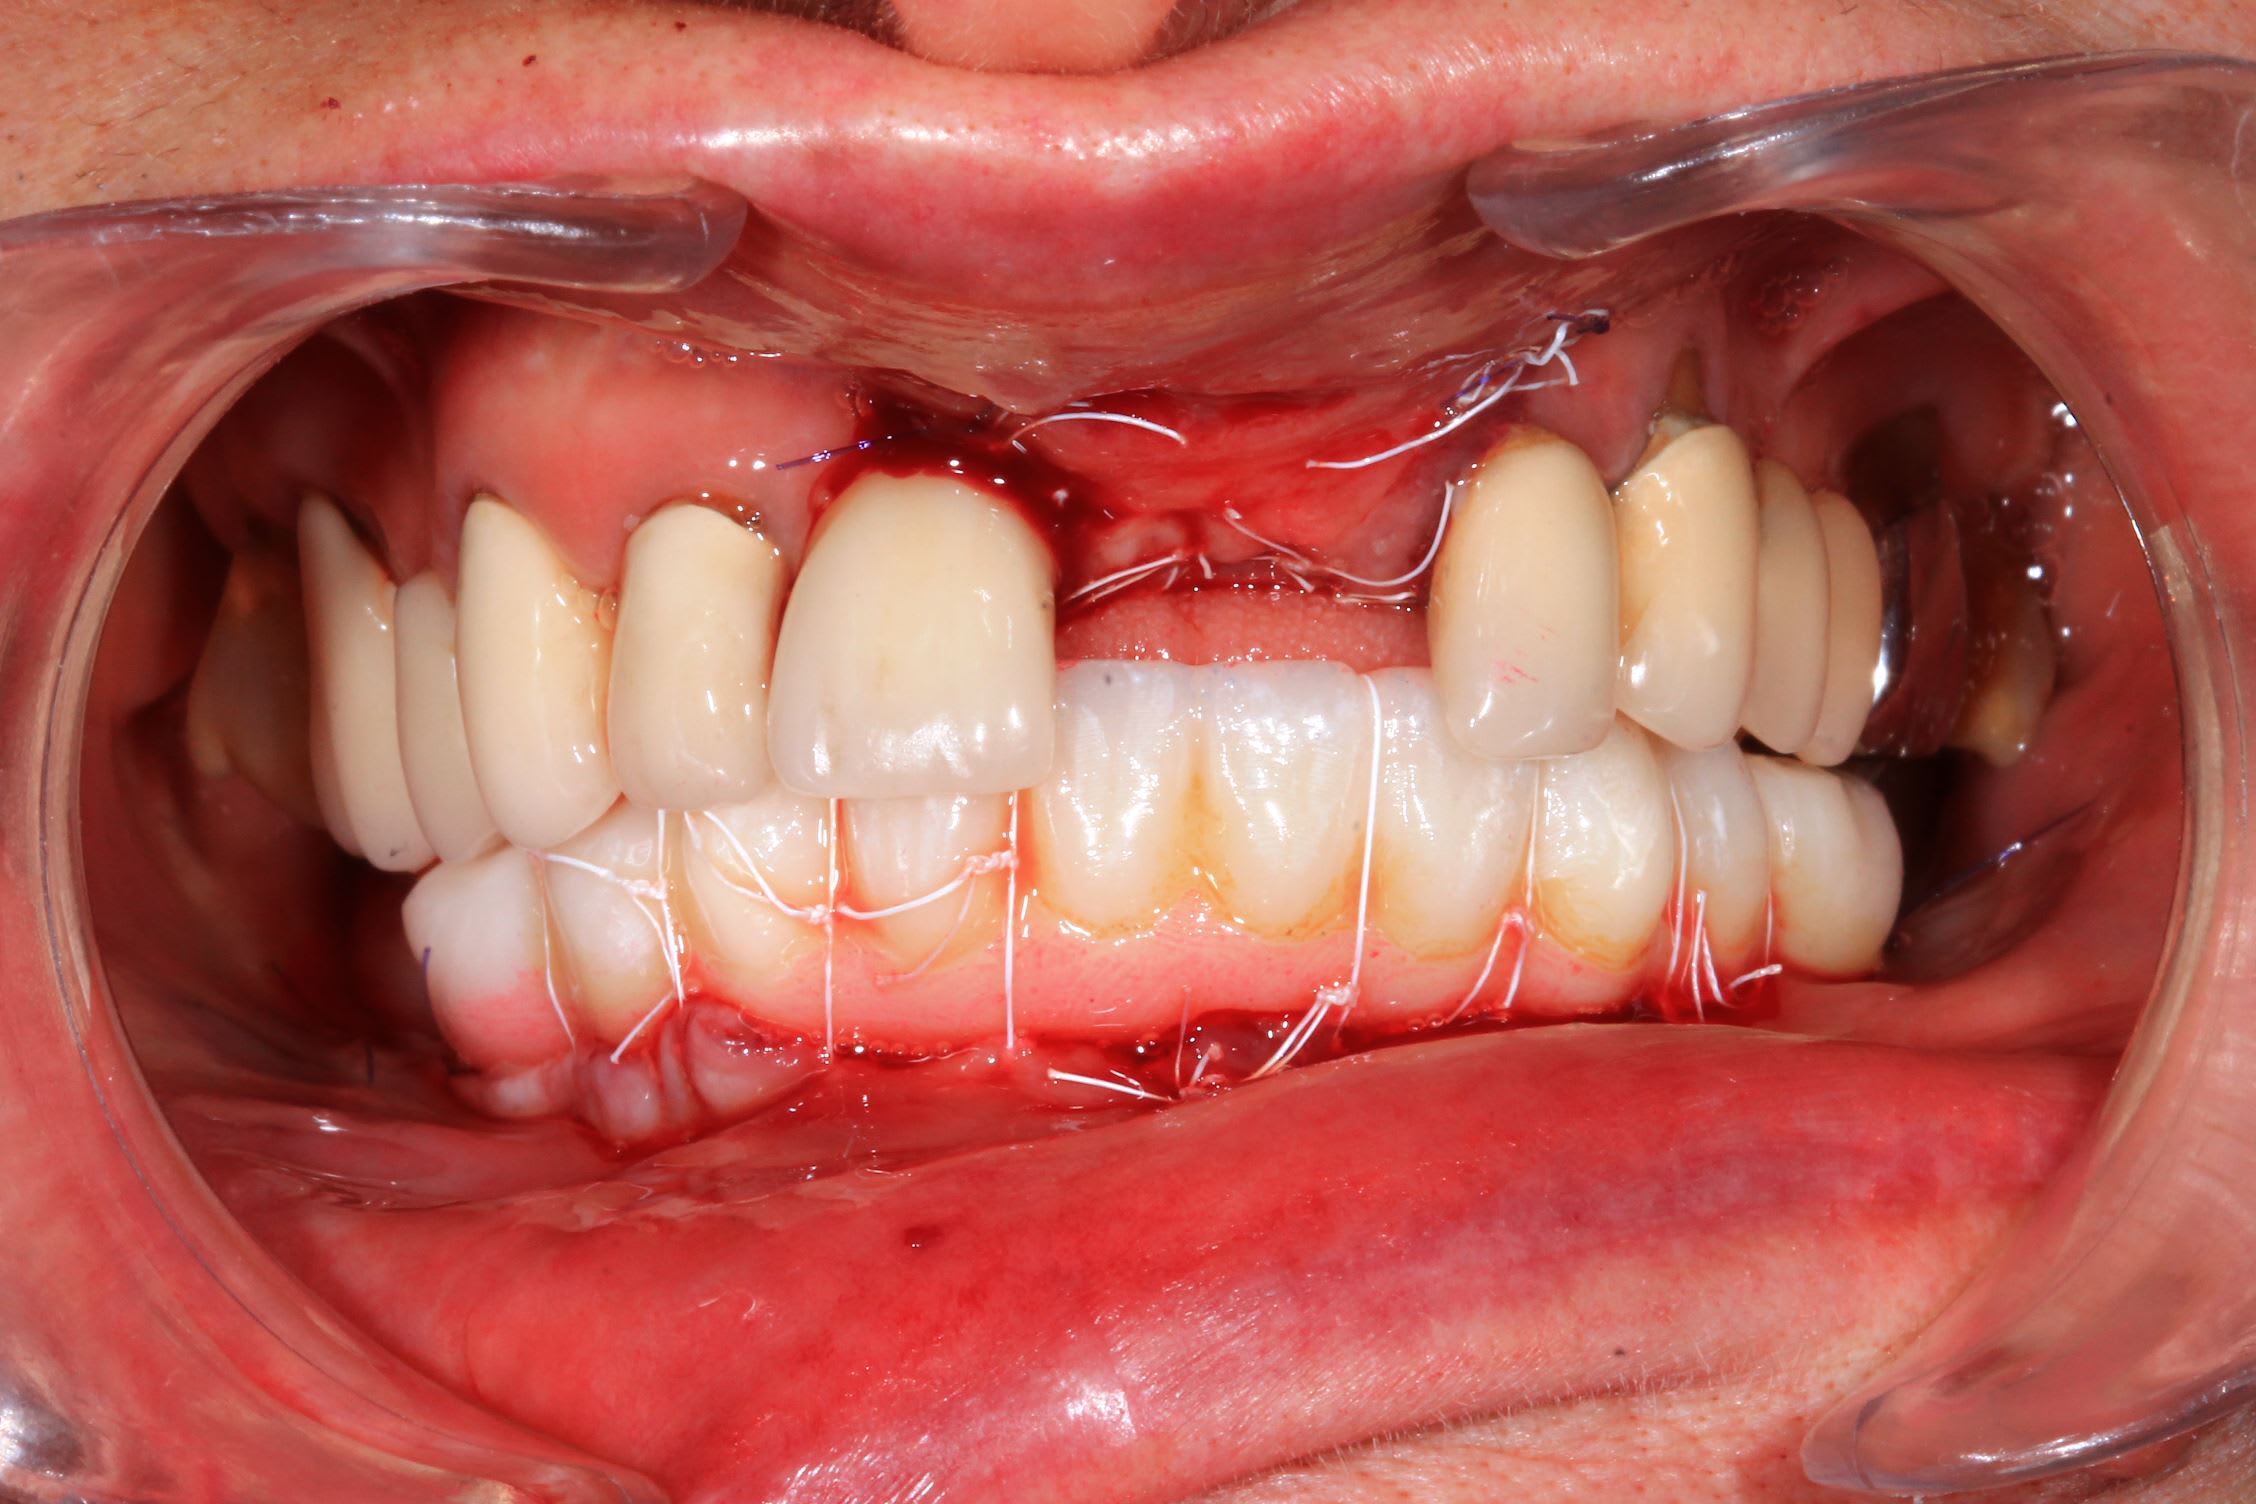

Un cas de mise en charge instantané, façon Dimitri Pascual.

Tres important pour la mise en charge instantanée : la precision : bien indexer les implants sur le guide en cas de piliers angulés.

Suture en matelassier horizontal sous le bridge + vertical sur le bridge : gain de gencive kératinisée .